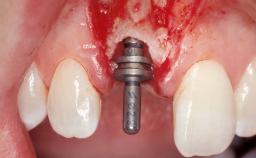

Early Placement of an Implant in a Maxillary Right Central Incisor Site

This 41-year-old female patient was referred to the clinic for the replacement of the right central incisor, since the tooth had developed a root fracture in the long axis that made extraction necessary. The healthy, non-smoking patient was first seen with the tooth still in place. A detailed Esthetic Risk Assessment was performed.The patient was worried about her dental esthetics and had high expectations for a successful treatment outcome from an esthetic point of view. The patient had a medium lip line that displayed parts of the gingiva in the anterior maxilla upon smile.

Type of Implants Two-Piece

Bone Augmentation Horizontal|Simultaneous

Augmentation Materials Autogenous chips|Xenogenous|Membrane

Bone Volume Deficient horizontally, allowing simultaneous augumentation

Esthetic Risk High